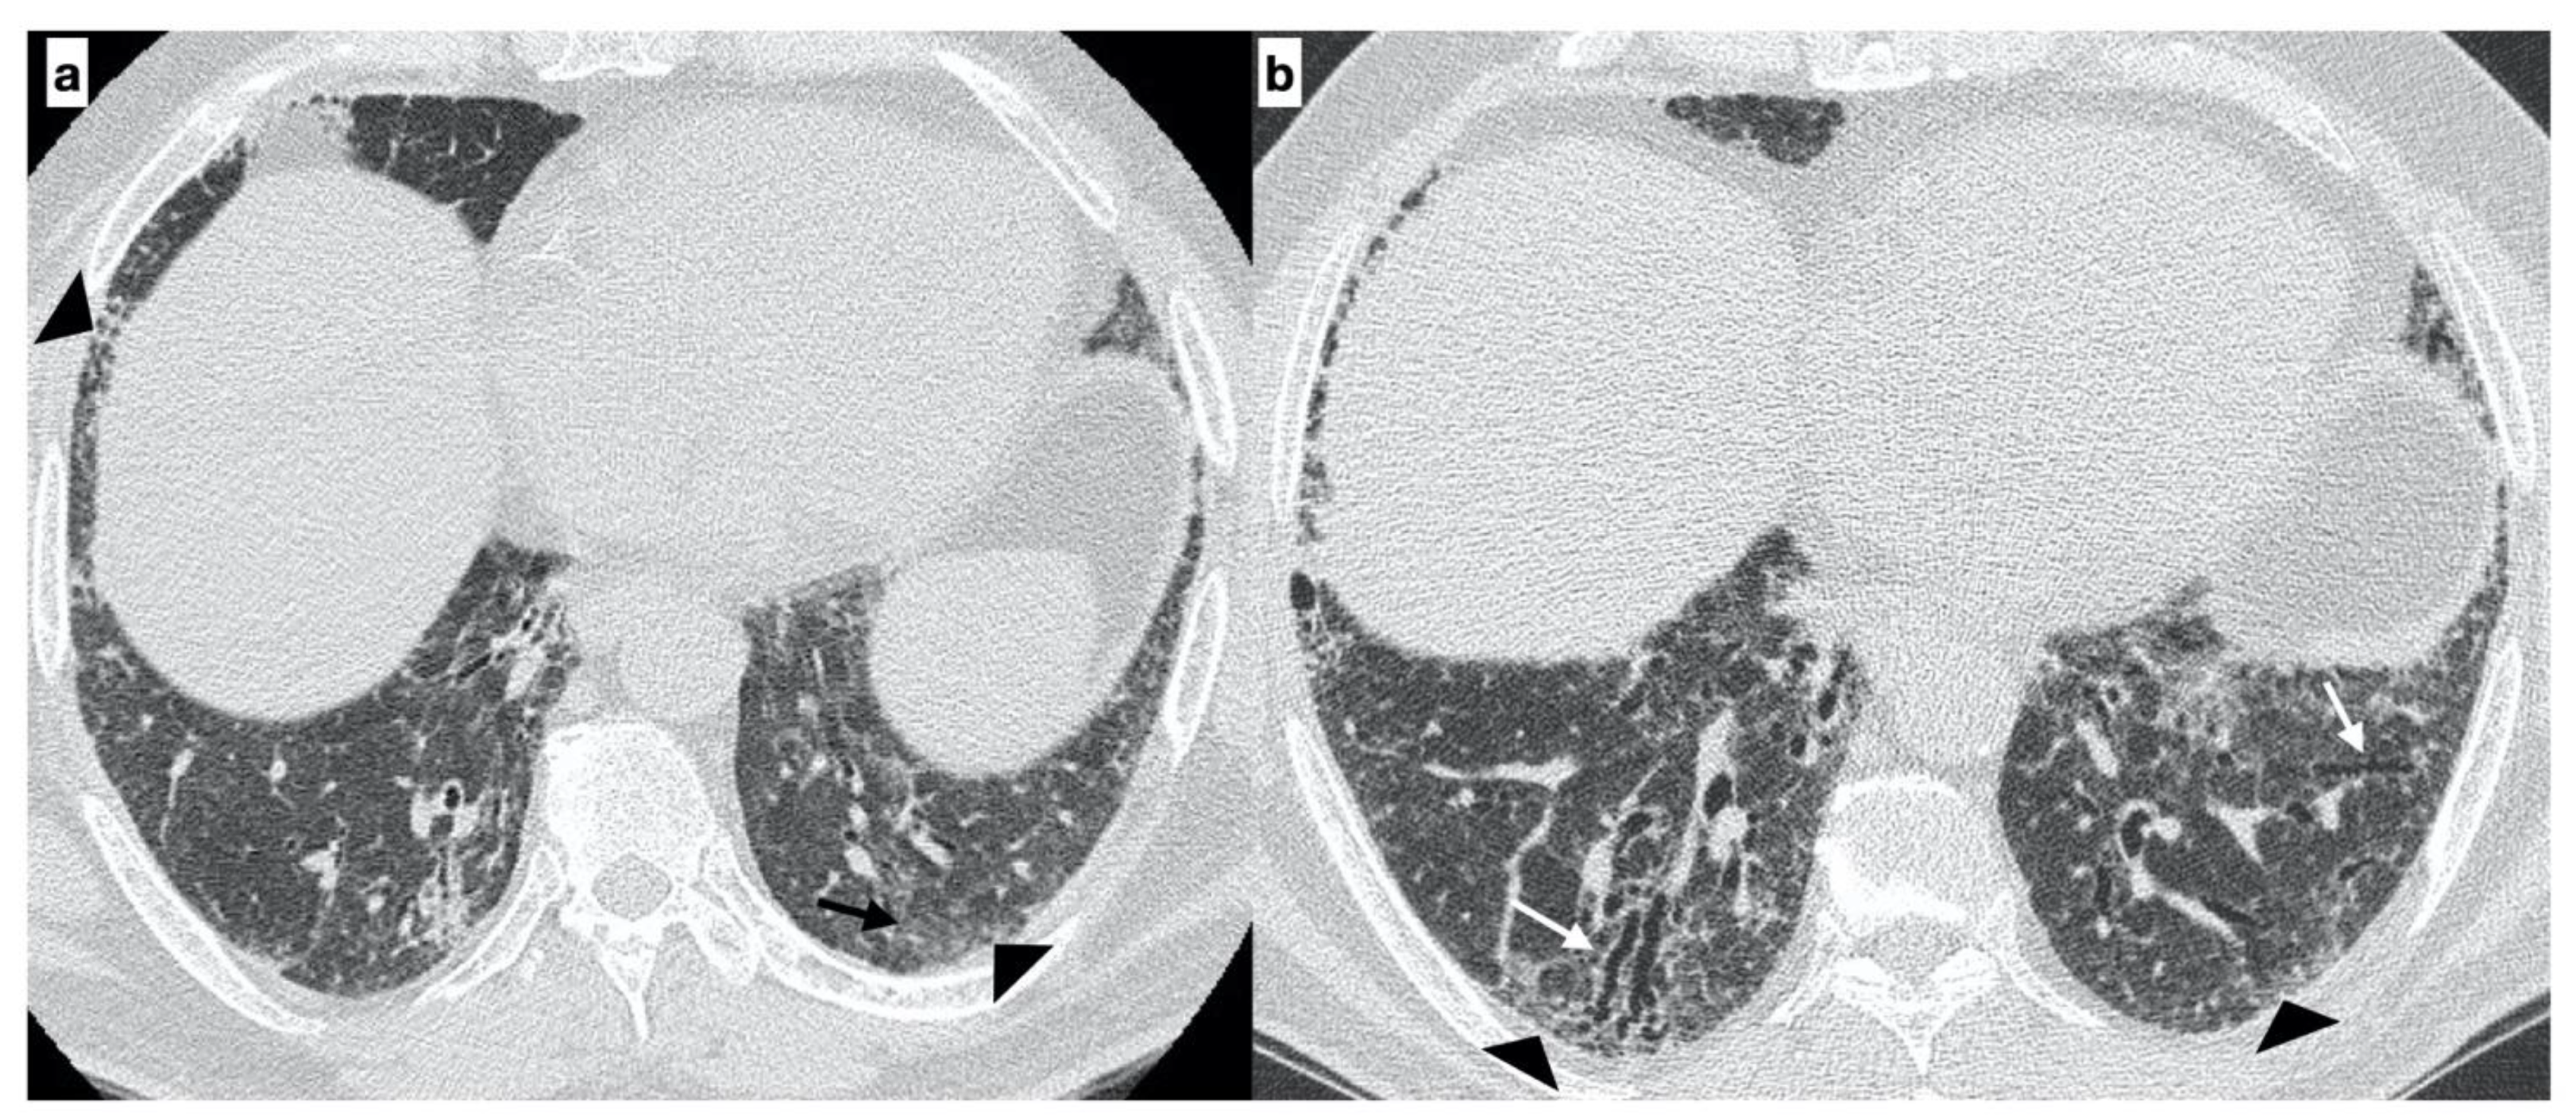

At diagnosis, there was a statistically significant difference in the HRTC pattern between the two groups: sporadic IPF patients had a predominantly typical UIP pattern compared to familial IPF patients (60.0% vs. 21.1%, respectively). There was a predominance of an alternative diagnosis HRTC pattern in familial IPF compared to sporadic IPF (31.6% vs. 2.2%, respectively) (see Figure 1, Figure 2 and Figure 3). The HRCT for 6/19 patients with a familial pulmonary fibrosis at the onset of symptoms had an alternative diagnosis pattern: this was due to the presence of a fibrotic nonspecific interstitial pneumonia (NSIP) pattern in 4/19 patients, whilst in 2/19 patients it was due to the presence of honeycombing with upper-mid lung distribution (see Figure 1). At the onset of symptoms, only 1/46 sporadic IPF patients had an alternative diagnosis HRCT pattern, due to the presence of honeycombing with upper-mid lung prevalence and mosaic attenuation; the definitive diagnosis of IPF was made by biopsy (see Figure 2 and Figure 4). After 2 years from diagnosis in the familial IPF group, we observed a slight increase in the typical UIP pattern at HRTC evaluation (see Figure 3 and Figure 5).

Figure 4. A 67-year-old male with “UIP pattern” on HRCT at the onset of respiratory symptoms. Axial HRCT plane shows honeycombing (black arrows) and reticulations (arrowheads) with a basal predominant distribution (a); traction bronchiectasis (white arrows) and distribution of alterations are better visible on the sagittal plane (b). Genetic analysis demonstrated the following types of mutations: SFTPA2, promoter-TERT, TERT.